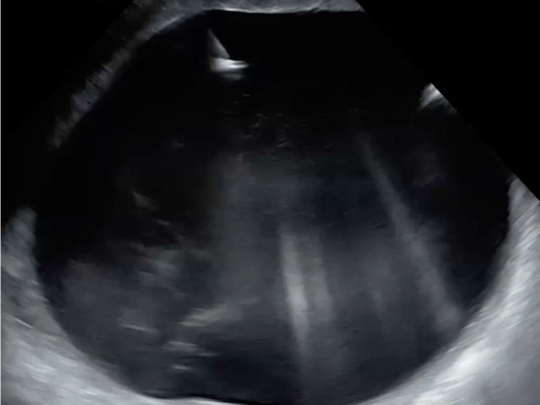

Spezielle Ultraschalluntersuchung des fetalen Gehirns

Die Untersuchung des kindlichen Gehirns stellt einen wesentlichen Baustein in der fetalen Fehlbildungsdiagnostik dar, auch bei uns in der Pränataldiagnostik und Schwangerenambulanz. Vor allem wenn es um spezielle Fragestellungen geht, wird eine noch detailliertere Untersuchung der Hirnstrukturen durchgeführt. Diese kann bei entsprechender Indikation durch eine vorgeburtliche Kernspintomographie (MRT) ergänzt werden.

Abbildungen: Normalbefund, fetales Gehirn in 3 Schnittebenen dargestellt